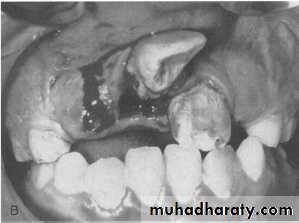

INTRUSIVE LUXATION

Diagnosis; teeth appear shortened, or in severe cases could appear missing, not mobile nor tender

Radiograph; root apex is displaced

apically PDL space is non-continuous